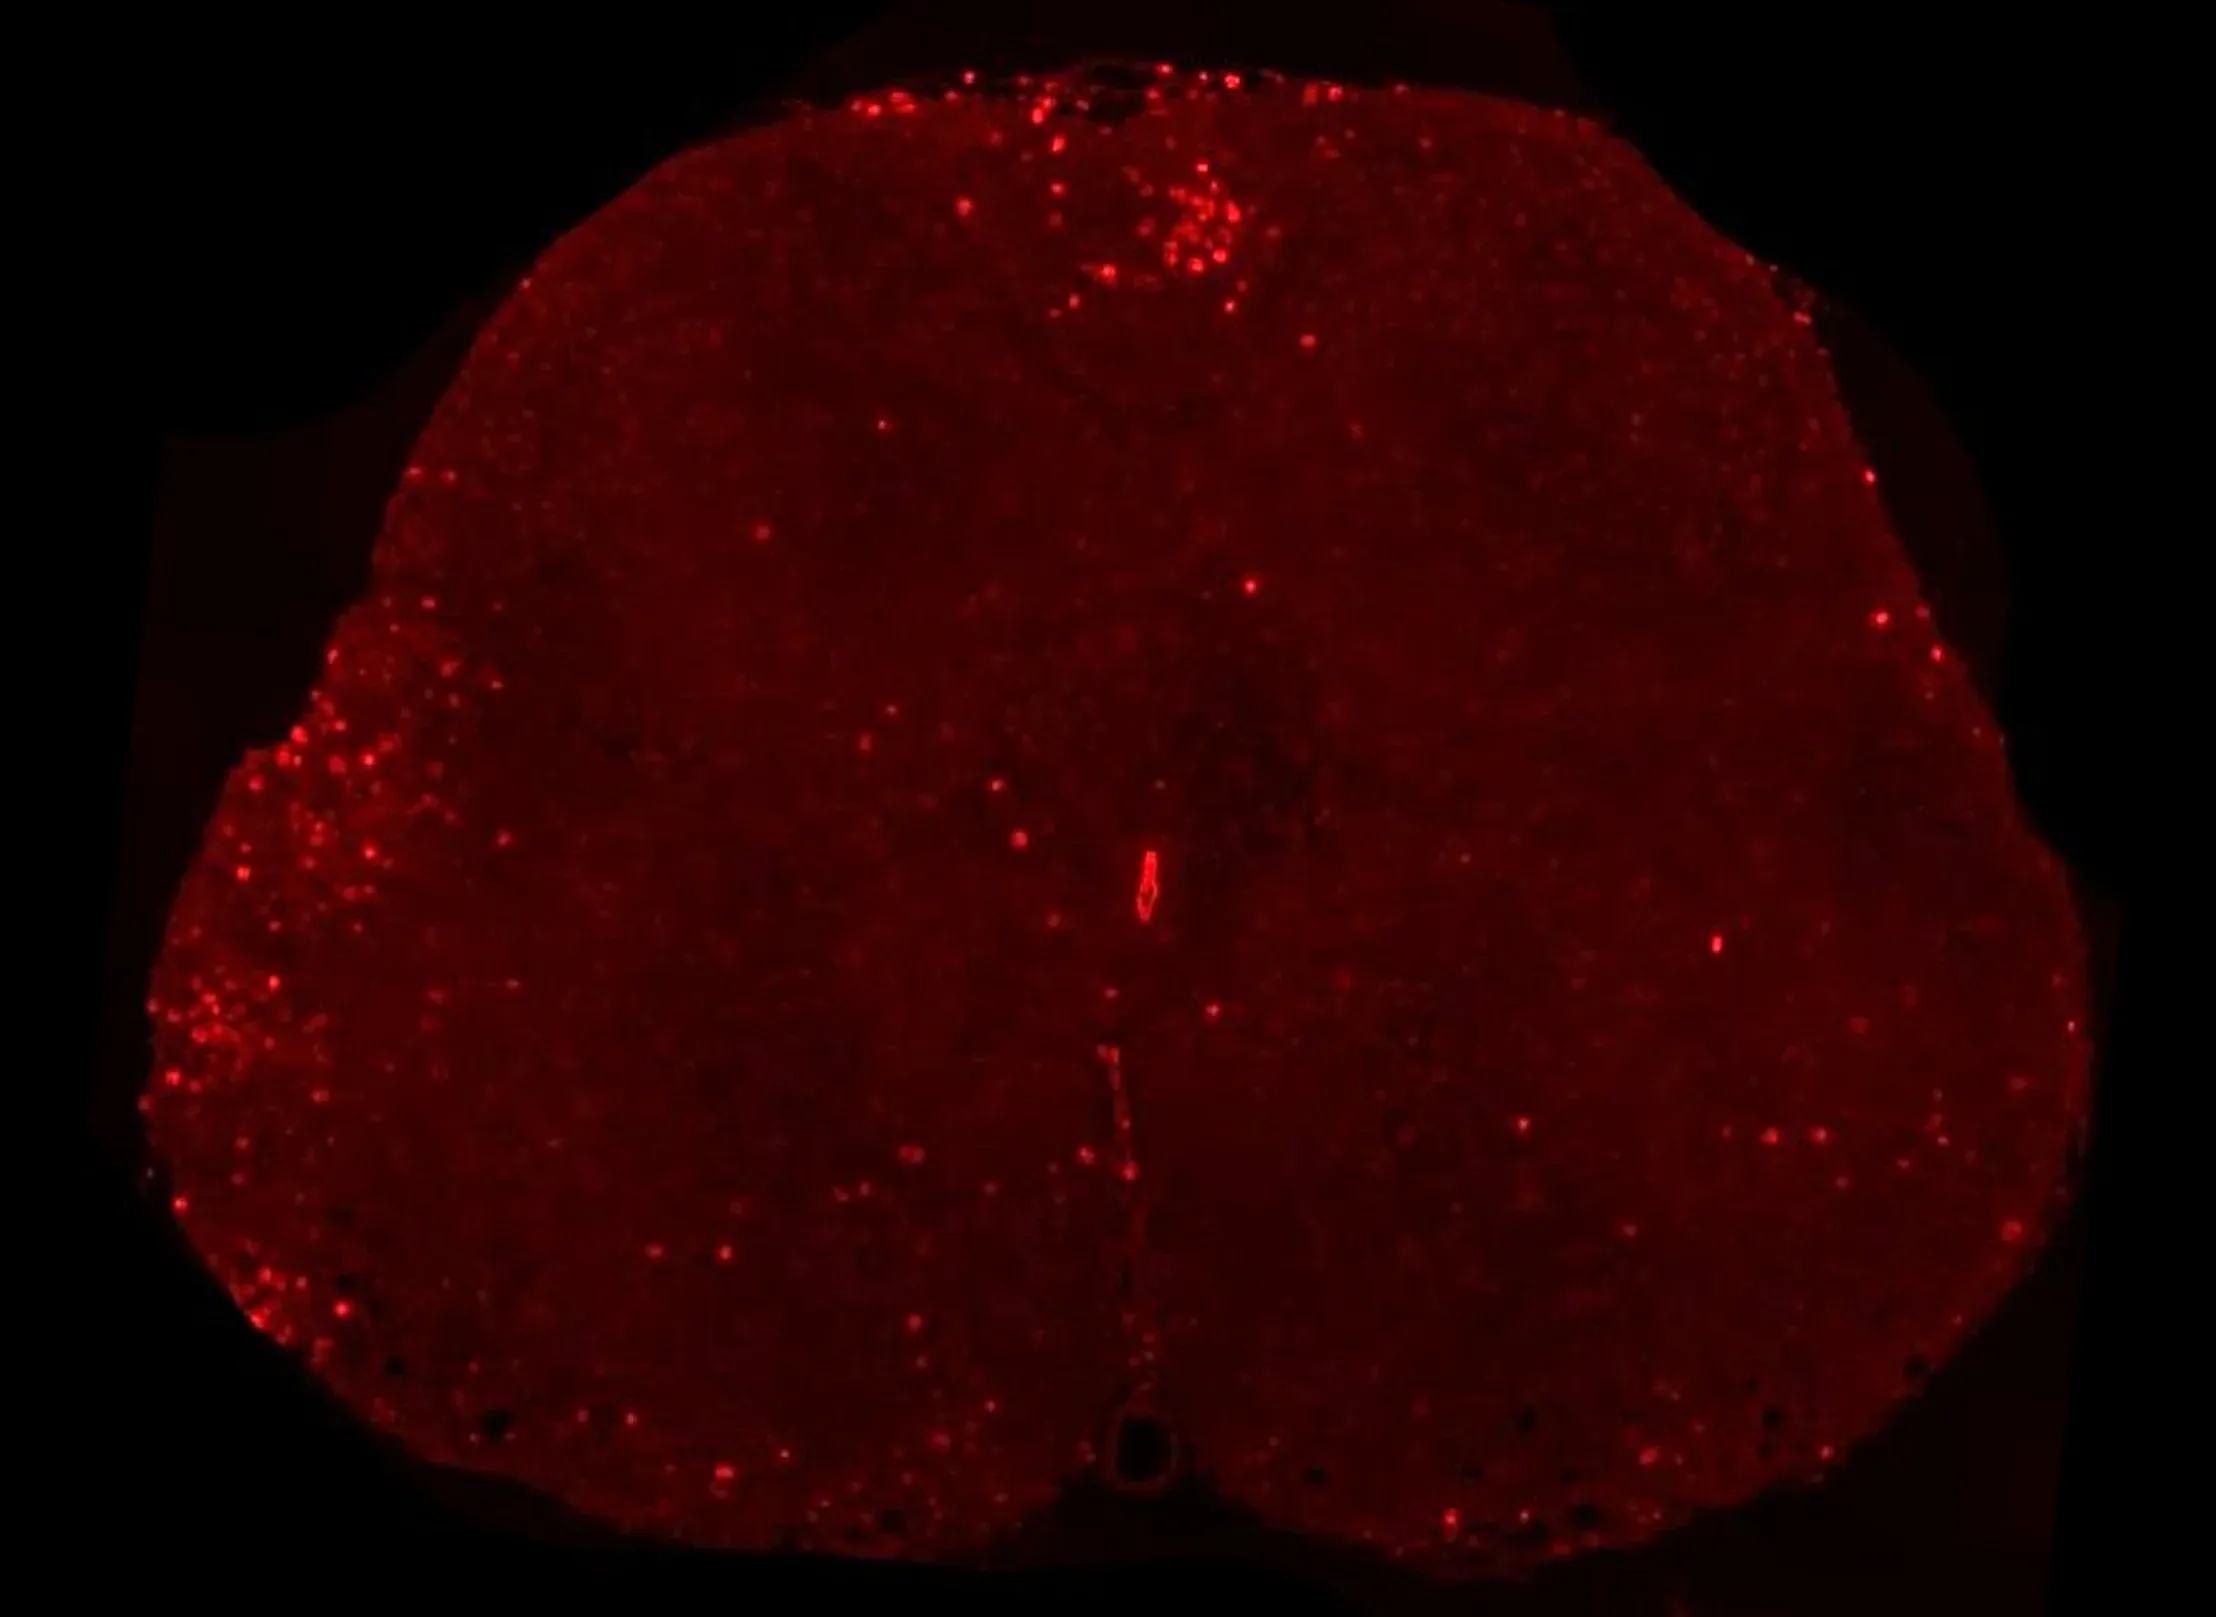

T lymphocytes infiltrating the spinal cord in the MOG35-55 EAE mouse model.

Peripheral Inflammation

EAE is an autoimmune mediated disease. As such, infiltration of T lymphocytes into the spinal cord is a characteristic feature of this model. Further, macrophages are also readily observed in EAE lesions along with resident microglia.